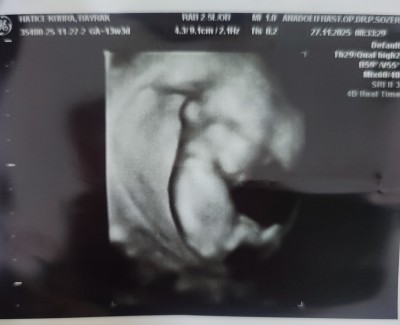

11 haftalık ve 13+5 haftalık ultrason görüntülerimiz doktor cinsiyette emin olamadi önce erkek sonra kız dedi ama sizin tahminleriniz neler?

Gebelik haftası 13+5

Kız hissettim

Kız sanki☺️